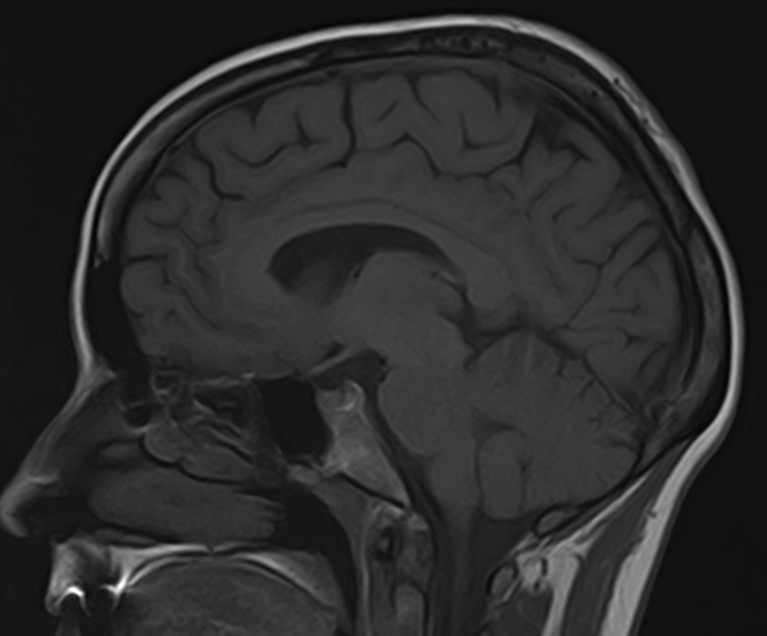

Для диагностики поражения черепно-мозговых нервов, а также оценки состояния окружающих их тканей и визуализации сосудистой сети головного мозга в клинике «Доступная медицина» проводится комплексное обследование МРТ головного мозга + Мр-ангиография головного мозга + МР-венография головного мозга + черепно-мозговые нервы. Данное обследование включает в себя несколько протоколов: стандартный – для оценки состояния всех структур головного мозга и дополнительные – для изучения очагов поражения черепных нервов и визуализации всей сосудистой системы головного мозга.

Исследования выполняются на современном высокопольном томографе экспертного класса TOSHIBA VANTAGE TITAN 1,5 Тесла, который использует разные режимы сканирования с толщиной среза от 1мм в различных плоскостях с последующей цифровой обработкой полученных данных для создания трехмерных изображений. МР-ангиография отображает состояние артериальной системы кровоснабжения головного мозга. МР-венография головного мозга позволяет детально изучить особенности венозного русла головного мозга.

Компьютерная программа обрабатывает данные, полученные при сканировании, и формирует объемные изображения как самого мозга, так и сосудистой системы в отдельности без прилегающих тканей. Методики применяются одновременно и взаимодополняют друг друга.

Данное комплексное исследование в большинстве случаев проводится с контрастным усилением, которое необходимо для улучшения визуализации черепно-мозговых нервов. Для этого внутривенно вводится препарат, содержащий гадодиамид (соли металла гадолиния) для получения изображений с высокой четкостью и контрастностью, что способствует ранней диагностике заболеваний головного мозга.